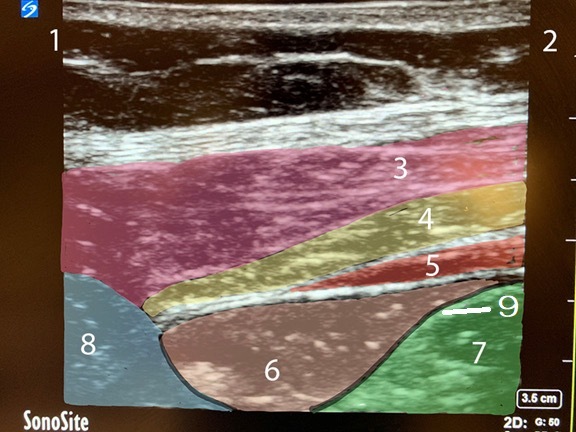

QL Block Anatomy 1 Image

1. Posterior

2. Anterior

3. External Oblique Muscle

4. Internal Oblique Muscle

5. Transverse Abdominis Muscle

6. Pararenal Fat

7. Peritoneum

8. Quadratus Lumborum Muscle

9. Transversalis Fascia